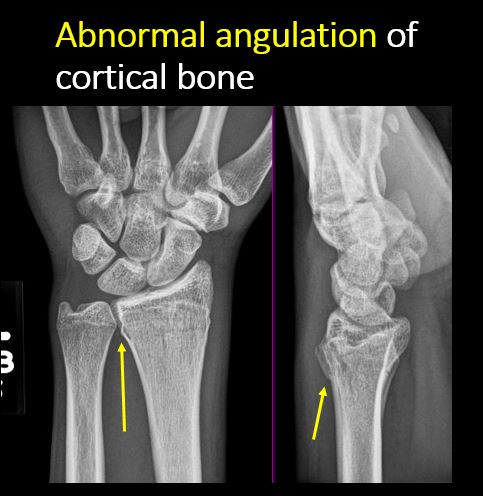

There is abnormal angulation of the cortical surface relative to the normal cortex. |

Yes | NA |